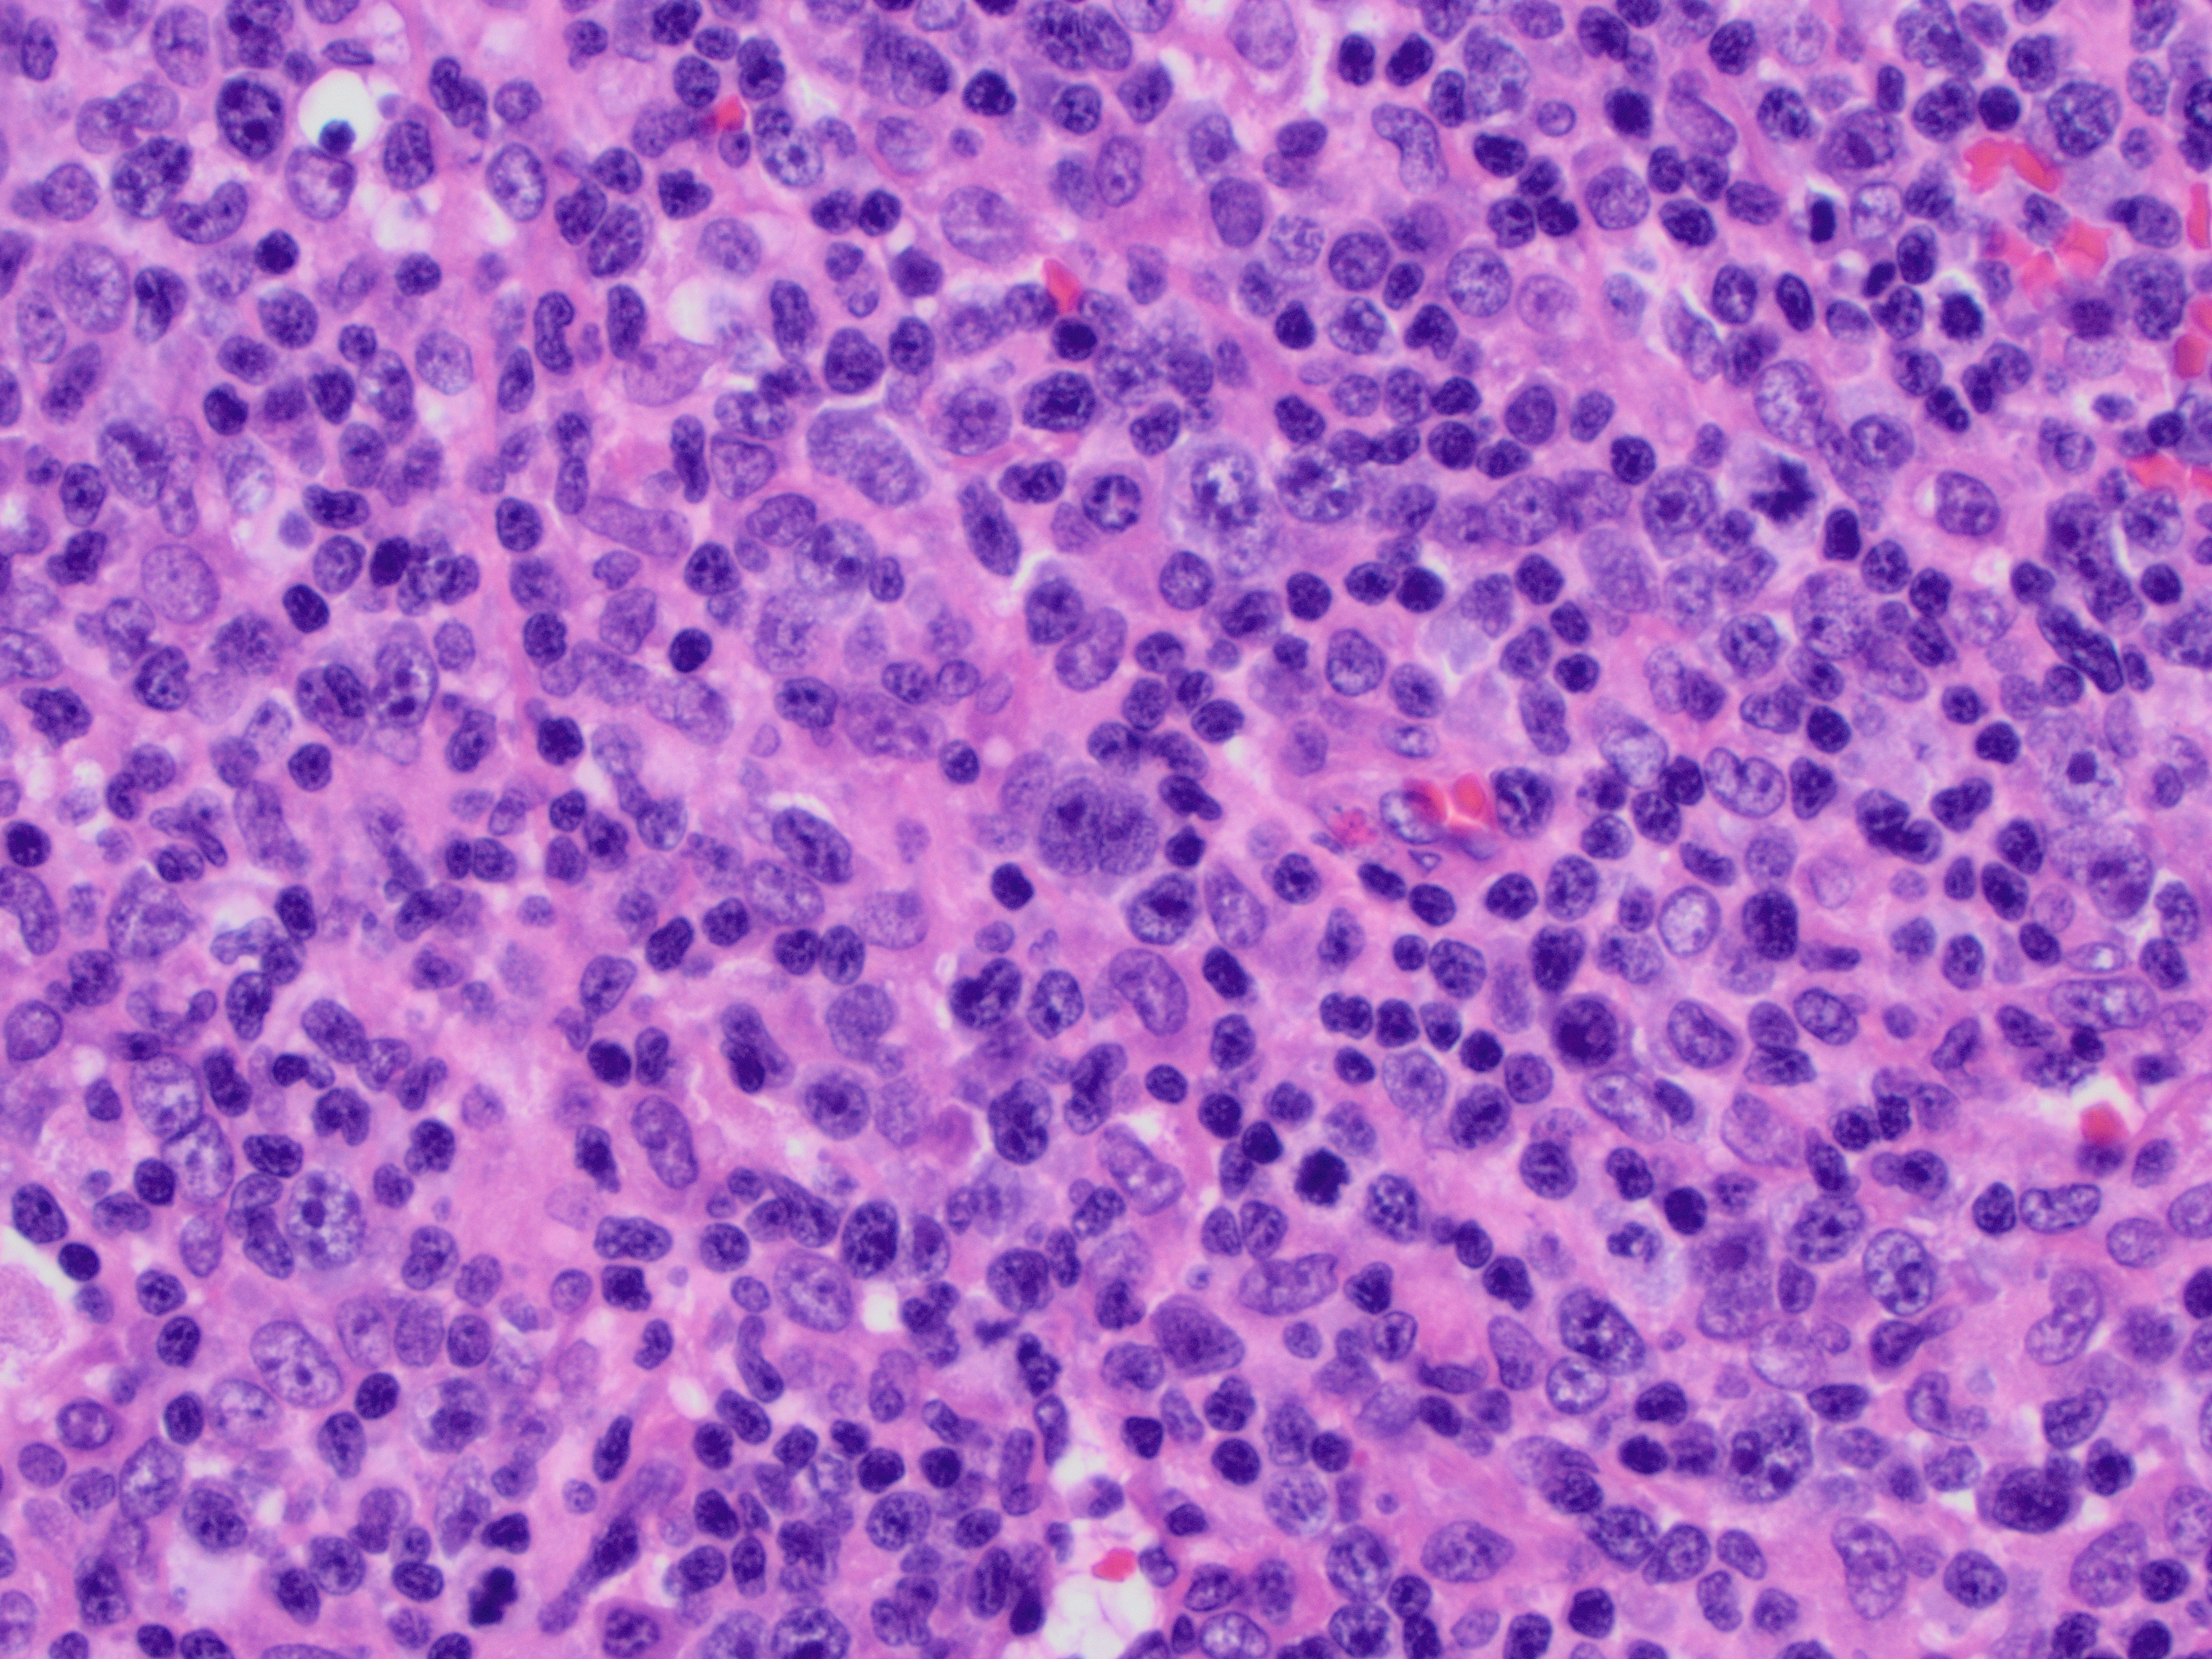

Case History:

A 64 year-old man with history of clear cell renal cell carcinoma s/p nephrectomy (2021) presents with scrotal pain and firmness. Ultrasound reveals a 2 cm solid lesion. Serum tumor markers (hCG and AFP) were normal. The tumor was negative for SALL4, OCT3/4, AFP, and showed focal patchy positivity for pancytokeratin (focal). PAX8 was weakly positive. Additional stains are displayed in the pictures.